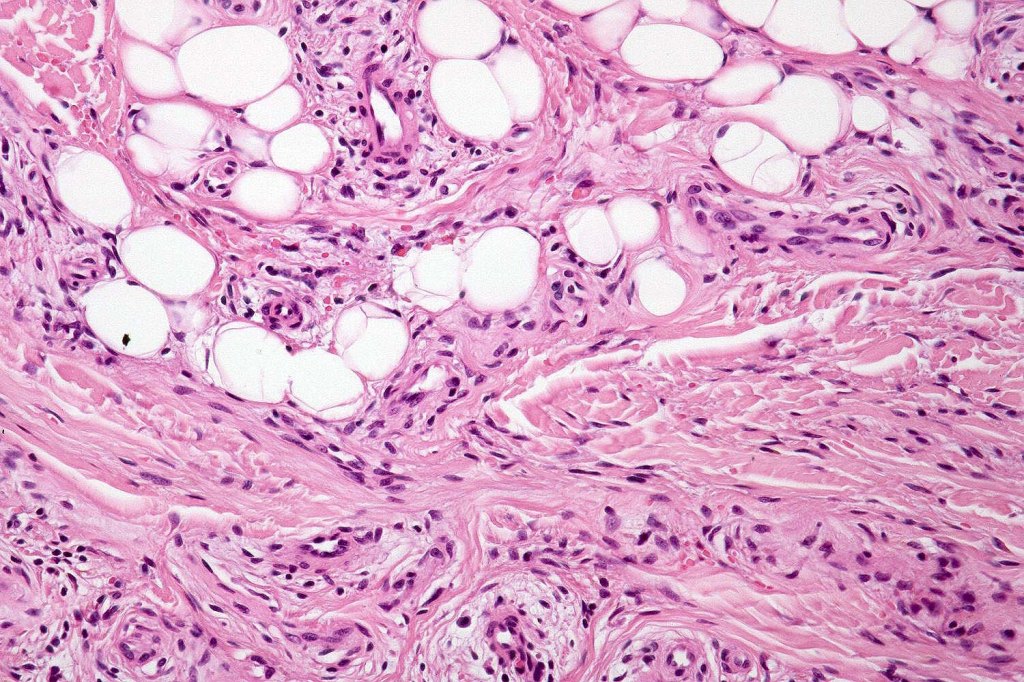

•An infundibular cyst is surrounded by laminated dermal collagen, elastic fibers, blood vessels, adipocytes & spindle cells separated from the adjacent dermis by a retraction artifact

•Exceptionally may show spindle cell lipoma-like features